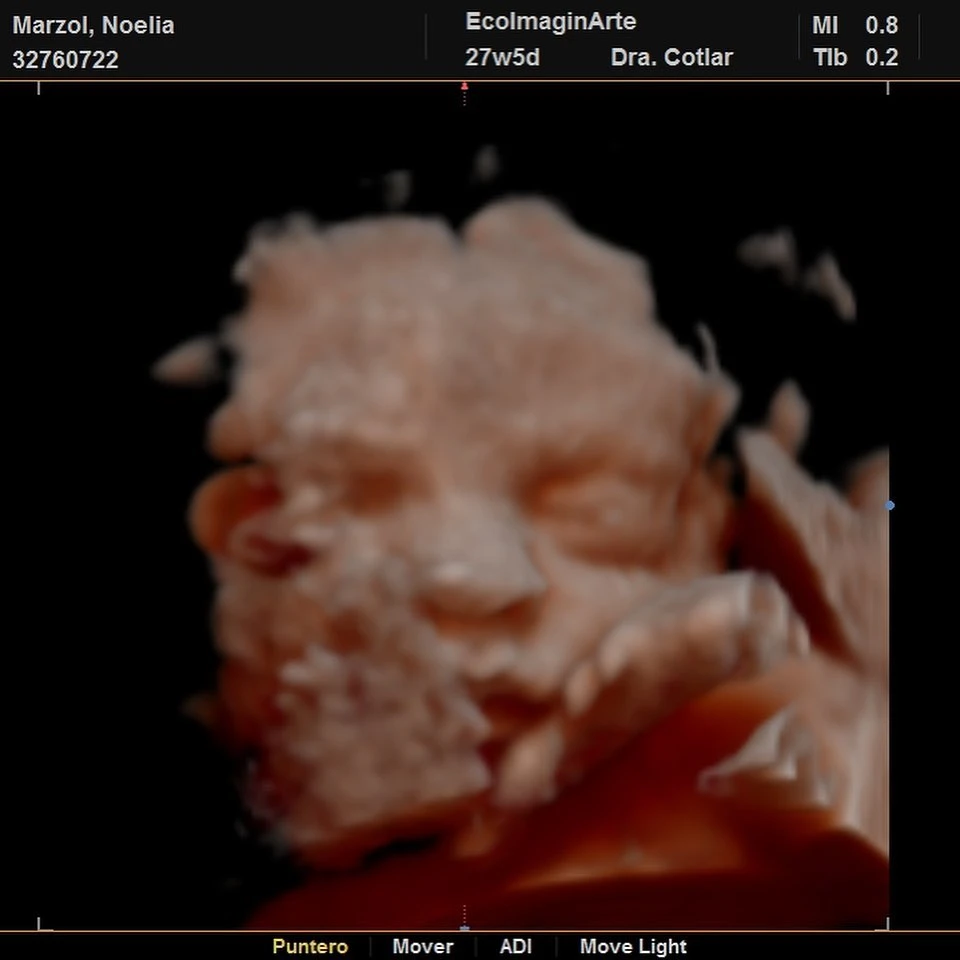

Ahora sorprendió a todos sus seguidores con dos imágenes muy tiernas de una ecografía de su hijo Donatello, a quien presentó en sus redes sociales.

Recuperada de coronavirus, Marzol tuvo que hacer aislamiento, pero por fortuna atravesó la enfermedad sin complicaciones ya que resultó ser asintomática. A modo de celebración, Noelia publicó la cara del pequeño Doni y estallaron los corazones en su cuenta de Instagram.

“Horas tratando de que se deje ver bien. Éste es Doni (aplastado por mi placenta)”, escribió la futura mamá debajo de las fotos de la eco 5D, donde también agradeció a la profesional a cargo.